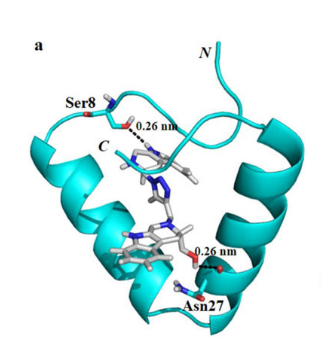

4.3.7 蛋白-小分子对接确定活性位点

4.3.11 刚性对接

4.3.4 预测药物与蛋白的结合位点

在分子动力学模拟中,预测药物与蛋白的结合位点是一个关键的步骤。这通常涉及到识别蛋白质表面的区域,这些区域可能与小分子药物发生相互作用并形成稳定的复合物。

这种预测通常使用各种计算方法来完成,包括分子对接,比较分析(比如通过比较已知的药物-蛋白质复合物结构),以及使用机器学习和人工智能算法。

分子对接是一种常用的方法,它通过模拟药物和蛋白质之间的相互作用,预测药物可能的结合模式和结合位点。在对接过程中,药物和蛋白质的相对位置和方向会被调整,以寻找能量最低(即最稳定)的药物-蛋白质复合物结构。

这些预测可以帮助研究人员理解药物如何与其目标蛋白质相互作用,以及如何设计更有效的药物分子。然而,需要注意的是,这些预测方法通常需要与实验数据相结合,以验证预测结果的准确性。

4.3.7 蛋白-小分子对接确定活性位点

在分子动力学模拟中,蛋白-小分子对接是一种常用的技术,用于预测小分子(例如药物分子)如何与蛋白质(例如酶或受体)相互作用。这种相互作用通常发生在蛋白质的活性位点,这是蛋白质上的一个区域,可以与小分子结合,从而影响蛋白质的功能。

对接过程通常涉及以下步骤:

首先,需要知道蛋白质的三维结构。这可以通过实验方法(如X射线晶体学或核磁共振)确定,或者使用计算方法预测。

然后,使用对接软件将小分子“对接”到蛋白质的可能的活性位点。这通常涉及计算不同的小分子姿态和位置,以及它们与蛋白质的相互作用能量。

对接结果通常会产生多个可能的小分子-蛋白质复合物。这些复合物然后可以根据他们的相互作用能量进行排名,以识别最可能的结合模式。

最后,可以使用分子动力学模拟来进一步研究小分子-蛋白质复合物的动态行为。这可以提供关于结合过程的详细信息,例如结合的稳定性,以及小分子和蛋白质之间的详细相互作用。

这些信息对于理解小分子如何影响蛋白质的功能,以及设计新的药物分子具有重要的价值。

4.3.11 刚性对接

在分子动力学模拟中,所谓的"刚性对接"(Rigid Docking)是一种假设参与对接的分子在对接过程中保持其原始的三维结构,即分子的所有原子的相对位置保持不变。这种方法通常用于对接过程的初步筛选阶段,因为它的计算成本相对较低。

刚性对接通常涉及将一个分子(通常是小分子或药物分子)在另一个分子(通常是大分子,如蛋白质)的表面上进行旋转和平移,以找到最佳的结合位点和姿态。在这个过程中,被认为是"刚性"的分子不会发生形状和构象的变化。

然而,刚性对接的一个主要限制是它忽略了分子在结合过程中可能发生的构象改变。在现实中,分子通常会在结合过程中发生某种程度的构象变化,以适应对方的结构。因此,尽管刚性对接在初步筛选阶段可能非常有用,但在需要更精确的预测时,可能需要考虑到分子的柔性,这就涉及到"柔性对接"或"半柔性对接"的方法。